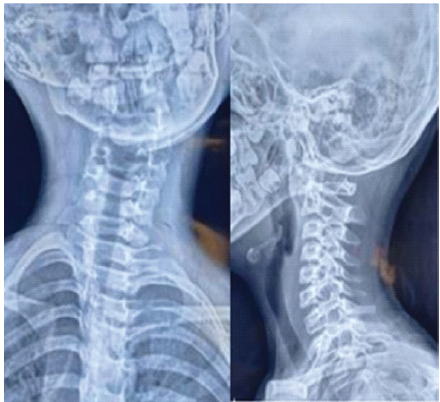

Plain radiographs demonstrated asymmetry of the lateral masses. Computed tomography (CT) scan confirmed Fielding Type II C1–C2 rotatory subluxation with anterior displacement of C1 (Fig. 2 and 3). Magnetic resonance imaging (MRI) showed persistent malalignment without spinal cord compression (Fig. 4).

Figure 2: Pre-operative anteroposterior cervical spine radiograph demonstrating asymmetry of the C1 lateral masses relative to C2, suggestive of atlantoaxial rotatory subluxation.